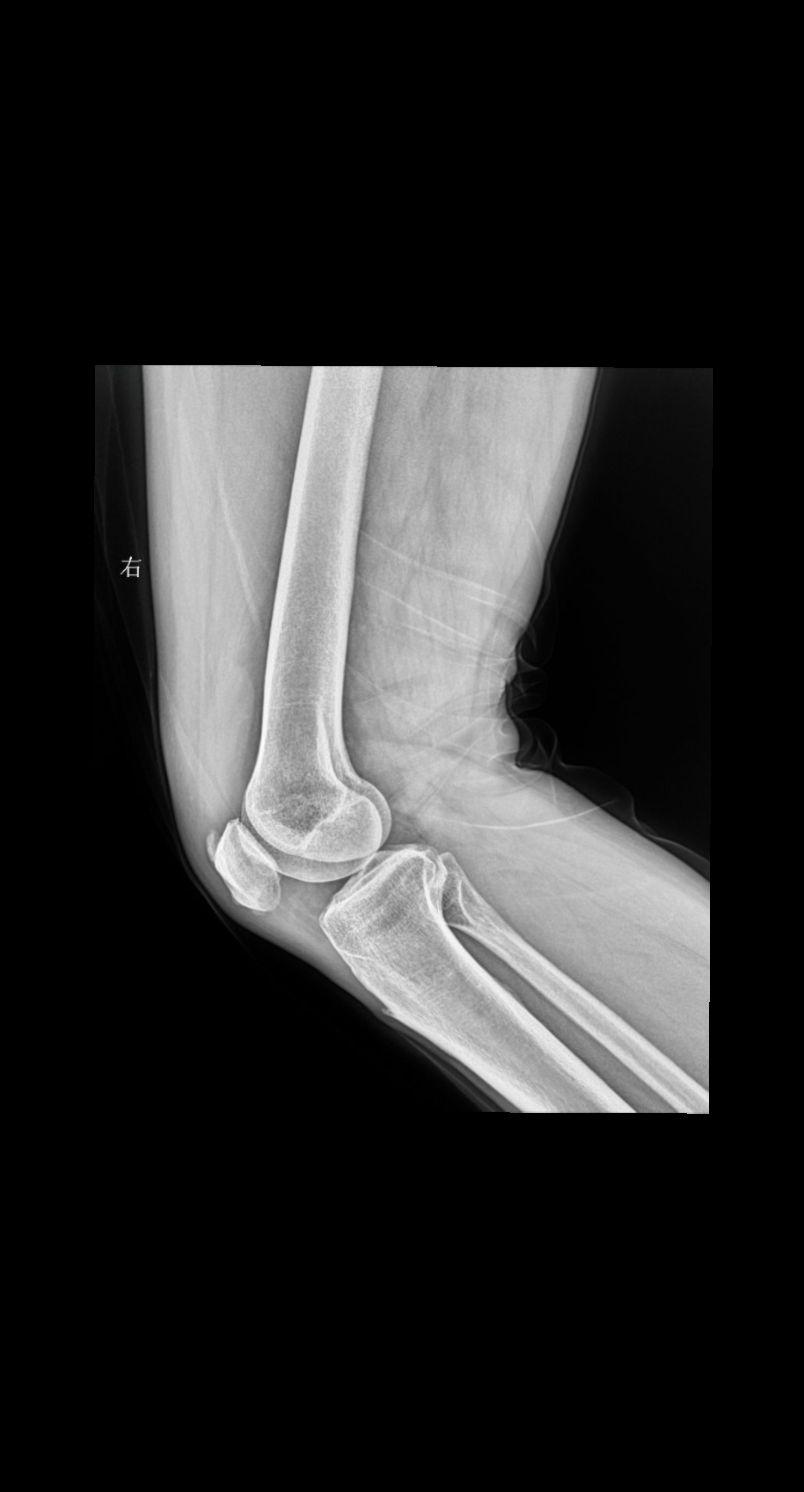

主诉 患者右侧膝盖疼痛 男47